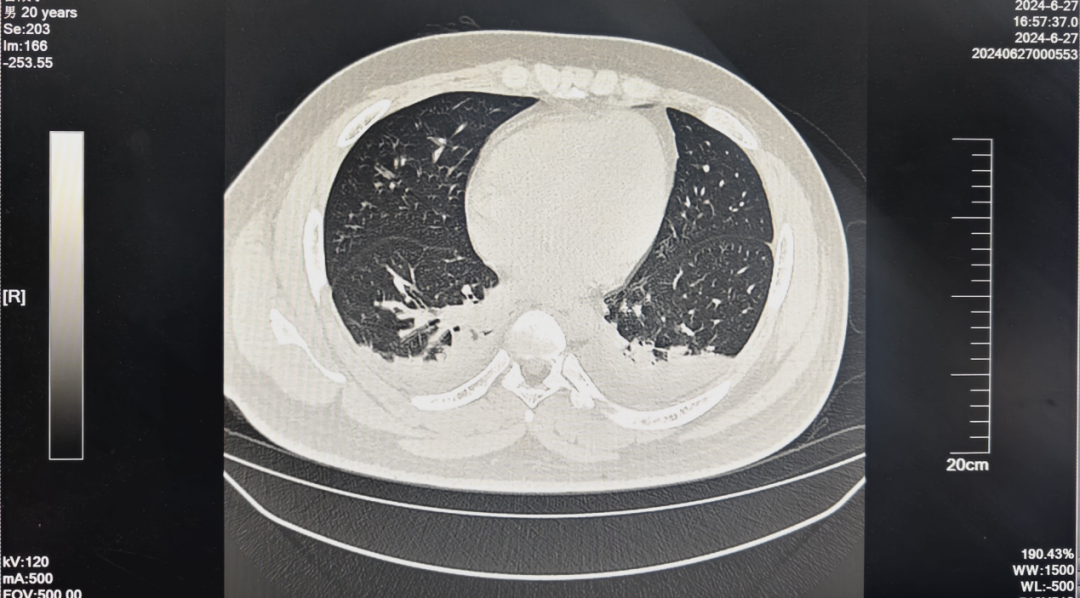

肺部的情況同樣不容樂觀。楊志前告訴“醫學界”,第三天的影像學檢查提示出現肺滲出,“這是典型‘百草枯肺’發生發展的徵兆,雖然當時患者的呼吸狀況、血氧飽和度等情況尚可,但根據我們的經驗,肺損傷一定還會持續加重,導致肺纖維化,最終引起呼吸衰竭。”

楊志前告訴“醫學界”,早在中毒後的第7天開始,患者雙肺出現明顯滲出,胸腔積液,導致雙肺膨脹不全,並出現呼吸急促,血氧飽和度下降等的表現。“第14天檢查時發現,他的肺損傷已經非常嚴重,肺表面出現大量實變,處於Ⅰ型呼吸衰竭的狀態。”

影像學檢查則發現,雖然患者肺部存在大面積實變,但肺纖維化的面積卻相對較小,“我們認為這和早期及時、精準地積極治療有關。只要沒發展成大面積肺纖維化導致嚴重的呼吸衰竭,肺損傷還是可以逐漸修復的,也無需進行肺移植。”

後續患者的恢復情況證實了團隊的猜想。從第3周起,患者呼吸趨於平穩,血氣分析表明呼吸衰竭情況得到改善,血氧飽和度也逐漸回到了95%以上。到了中毒後的第29天,胸部CT檢查顯示,患者雙肺損傷無再進展,反而是滲出得到了吸收,左側胸腔積液明顯減少。